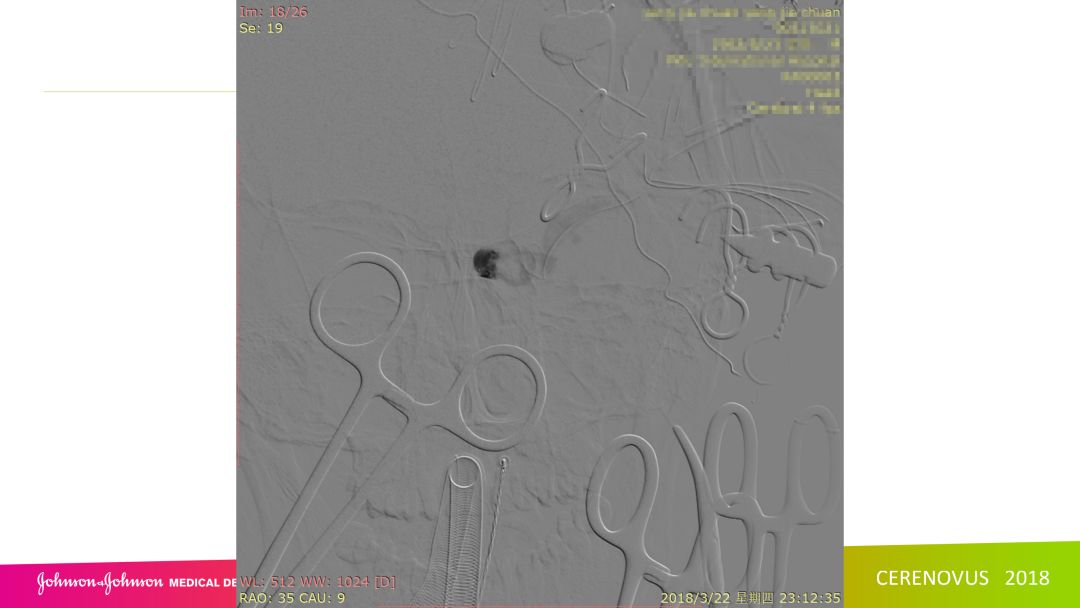

复合手术治疗海绵窦区硬脑膜动静脉瘘一例